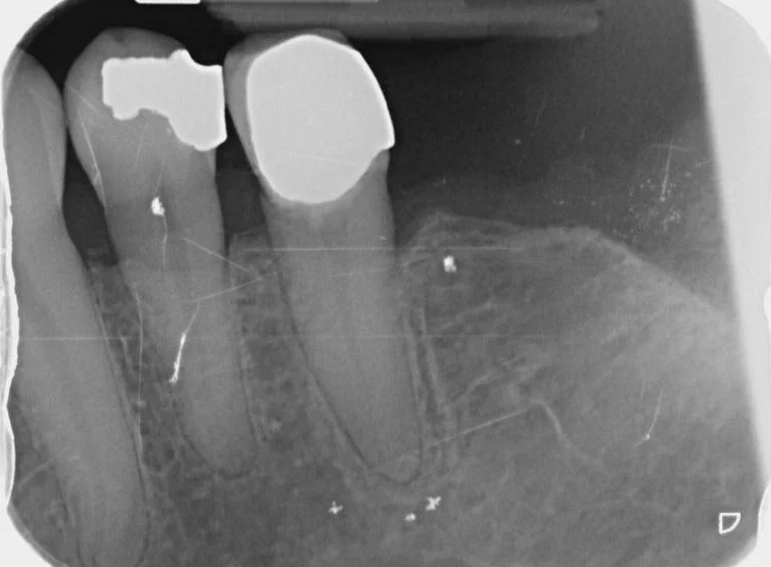

Case 18 – Prosthodontics

Extraction of failed bridge and temporary denture.